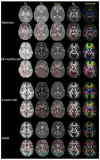

Diffusion tensor imaging (DTI) is an MRI technique that can measure the macroscopic structural organization in brain tissues. DTI has been shown to provide information complementary to relaxation-based MRI about the changes in the brain's microstructure. In the pediatric population, DTI enables quantitative observation of the maturation process of white matter structures. Its ability to delineate various brain structures during developmental stages makes it an effective tool with which to characterize both the normal and abnormal anatomy of the developing brain. This review will highlight the advantages, as well as the common technical pitfalls of pediatric DTI. In addition, image quantification strategies for various DTI-derived parameters and the normal brain developmental changes associated with these parameters are discussed.